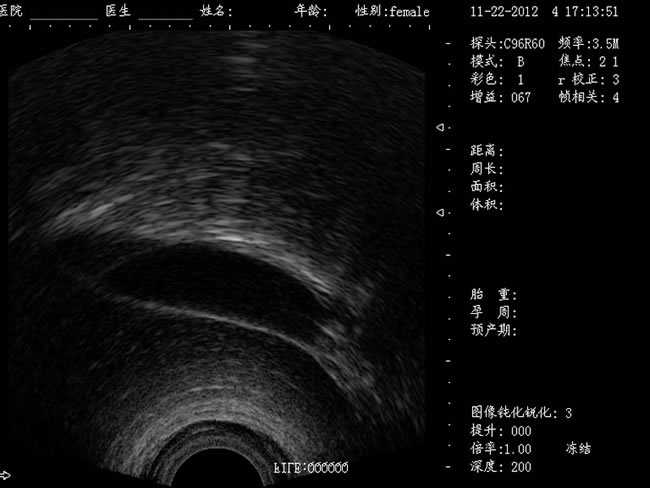

婦產科手術監視儀-可視人流機掃描角度:

a) 6.5MHz腔內探頭:152º可視可調;